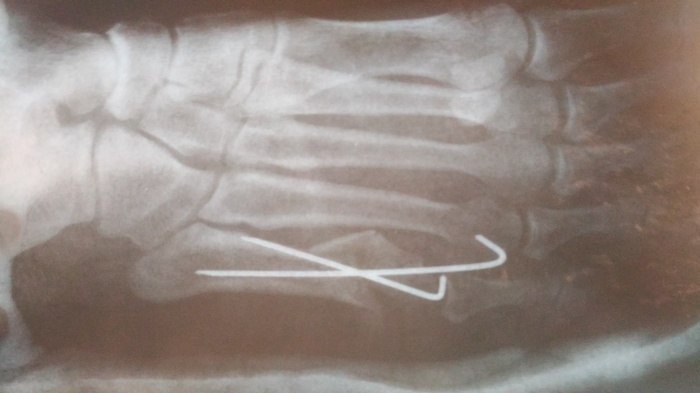

28 мая мой братик 40 лет от роду решил поиграть в бадминтон и сломал себе ногу, а точнее пятую плюсневую кость. В травмпункт мне удалось затащить его только 31 мая и то с трудом, так как я на 11 лет младше и давление на него оказывать сложновато. Там сделали снимок

и сказали срочно ехать в приемный покой во Вредена что бы там делали репозицию и иммобилизацию))) проще говоря что бы как то зафиксировать косточки с отломками и наложить лангету.

Во Вредена предложили три варианта поставить либо спицы, либо пластину либо вообще просто напросто загипсовать. Ложится в больницу брат не захотел, так как работает на дому(архитектор), а из больницы работать сложновато (возможно зря), решили поставить спицы и вот такая картинка получилась

сказали приехать в травмпункт на следующий день для перевязки.

Отсидев в очереди два часа (что еще не так много на самом деле), мы зашли в кабинет к врачу, не дав и слова сказать он начал на повышенных тонах отчитывать брата рассуждая, а стоит ли вобще брать его на прием. Никаких оправданий он выслушивать не захотел, говорил все время на повышенных тонах брат вышел из кабинета, так как он разозлился от такого обращения и сказал, что вобще ни к какому врачу не пойдет. Пока суть да дело, я договорилась что нас примет дежурный врач. На приеме выяснилось, что у брата произошло смещение отломка

Сказали что такое случается и предложили съездить во Вредена на консультацию о том, что делать дальше.

Вот собственно вчера были на консультации, доктор увидев снимки спросил кто сотворил сей ужас (про спицы). Сказал, что при таких переломах спицы на закрытую не ставят, нужно обязательно делать операцию, ставить либо пластинку либо шуруп, в зависимости от обстоятельств. А так одна спица немного кость держит, а другая вобще ничего не фиксирует. Операция платная и дорогая соответственно, за деньги мы к сожалению не можем себе ее позволить. У подруги (она врач) узнавала - бесплатно можно сделать, но тут 50 на 50, как она сказала скорее всего соберут плохо. Можно по направлению делать во Вредена и оплатить палату, что бы не так долго очередь ждать. Можно вообще ничего не делать, но тогда сказали что возможно будут проблемы при ходьбе, так как кость опорная, а в последствии могут быть проблемы с позвоночником.